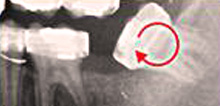

Strahlungsarmes modernstes, digitales Röntgen

Obwohl unsere Röntgentechnik mittlerweile so ausgereift ist, dass die Strahlendosis einer Aufnahme weniger als ein Fünftel der Strahlendosis während eines Transatlantikfluges ausmacht, verringern wir die Gesamtexposition indem wir so wenig Aufnahmen wie möglich anordnen, natürlich stets unter Ausblendung besonders strahlungsempfindlicher Gewebe